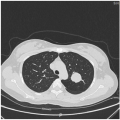

影像学:左肺上叶见类圆形肿块影,大小约2.9cm×2.6cm,边界清晰,密度均匀,CT值约49Hu,增强后病灶周围可见肺静脉包绕。

影像学检查:(点击查看大图)